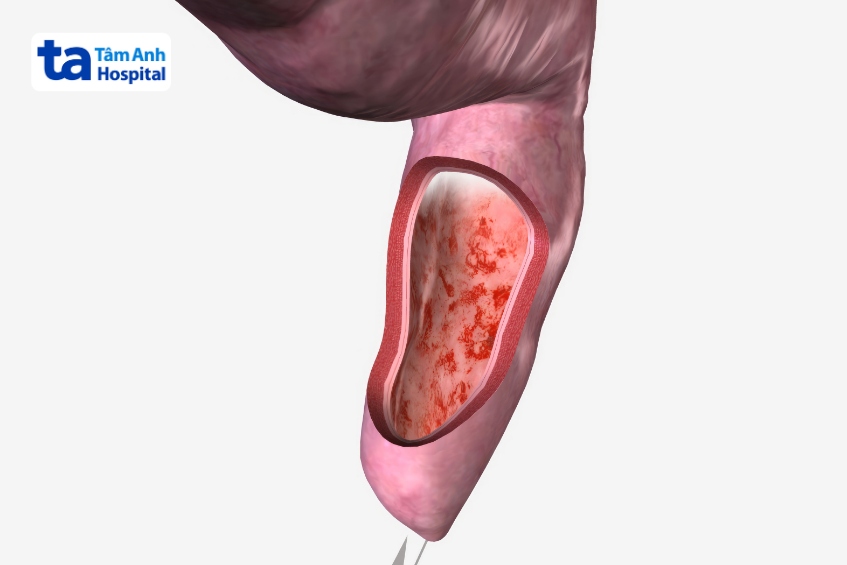

Trực tràng là một ống cơ nối với phần cuối của đại tràng. Phân khi đi ra khỏi cơ thể, phải di chuyển qua trực tràng. Viêm trực tràng là tình trạng niêm mạc trực tràng bị viêm, có thể gây đau trực tràng, chảy máu, tiết dịch, tiêu chảy và muốn đi đại tiện thường xuyên. Các triệu chứng bệnh có thể xảy ra và biến mất trong thời gian ngắn (cấp tính) hoặc diễn tiến thành mạn tính.

Viêm trực tràng thường gặp ở những người cơ địa dễ mắc các bệnh nhiễm trùng, hoặc các bệnh lây qua đường tình dục hoặc do thuốc. Một số ít trường hợp viêm trực tràng có thể do các nguyên nhân do bệnh viêm ruột mạn (bệnh Crohn hoặc viêm loét đại tràng). Một số trường hợp có thể do tác dụng phụ của phương pháp xạ trị điều trị ung thư.